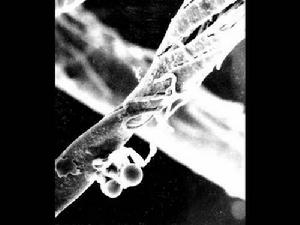

嬰兒皮膚念珠菌病SEM照片念珠菌屬中約有8種菌能引起人體致病。但白色念珠菌(canididaalbicans)為常見的。致病菌毒力最強,其它幾種念珠菌因致病力弱,較少引起感染,只有當人體免疫力特別低下時,這些念珠菌才會單獨或與白色念珠菌協同致病。